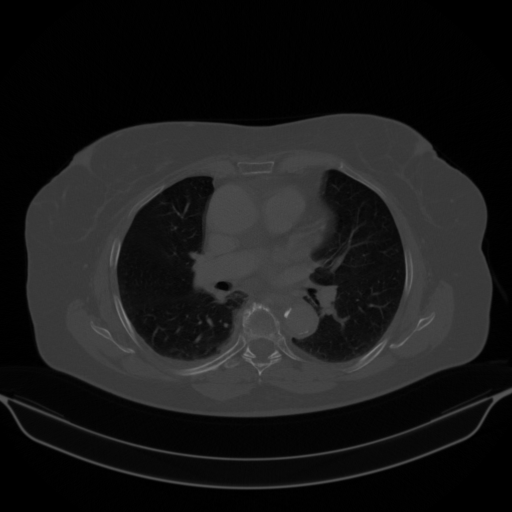

Image Grid

4Γ—3 grid: Rows show different image types (Original NATIVE, Reconstructed NATIVE, Original VENOUS, Generated VENOUS), Columns show windowing techniques (No Window, Lung Window, Mediastinum Window)

Original NATIVE CT scan (input)

Mediastinum window (WL 40, WW 400 β†’ Low βˆ’160, High +240)

Generated VENOUS CT scan (A→B translation)